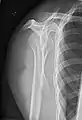

شانهها

تصویر AP سطح اریب خلفی ۴۰ درجه پس از Grashey

بدن باید حدود ۳۰ تا ۴۵درجه نسبت به شانه چرخانده شود تا تصویربرداری انجام شود و بیمار در حالت ایستاده یا نشسته اجازه میدهد دستانش را آویزان کند. این روش شکاف مفصلی و تراز عمودی نسبت به حفرات را نشان میدهد.[16]

_X-ray_of_a_normal_shoulder.jpg.webp)